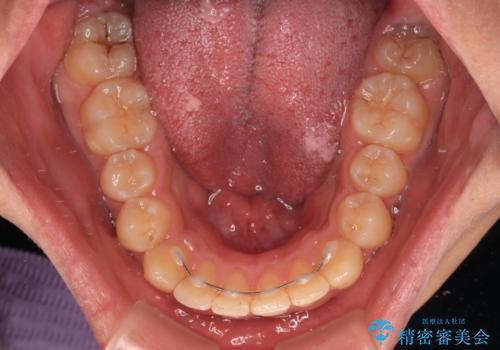

- 矯正装置

- メタルブラケット

上顎歯列全体がスムーズに後方移動でき、1年で治療を終えることができました。

- 矯正治療後の保定が不十分だと後戻り(元の位置に戻ろうとする動き)をします